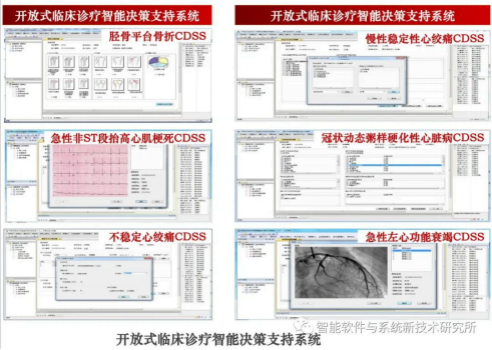

2. 面向医疗大数据的智能化分析与决策支持平台

形成基于多智能体的智能化数据处理与决策支持技术,成功应用于分析医疗大数据价值提供个性化诊疗服务。依据临床路径,规范化医师诊疗行为,同时模拟医学专家的决策过程,提出科学的、具有执行效果的诊疗方法。系统还集成临床指南检索与查询、诊疗方案反馈等应用模块,采用开放式管理平台,易于更新知识和拓展新病种。